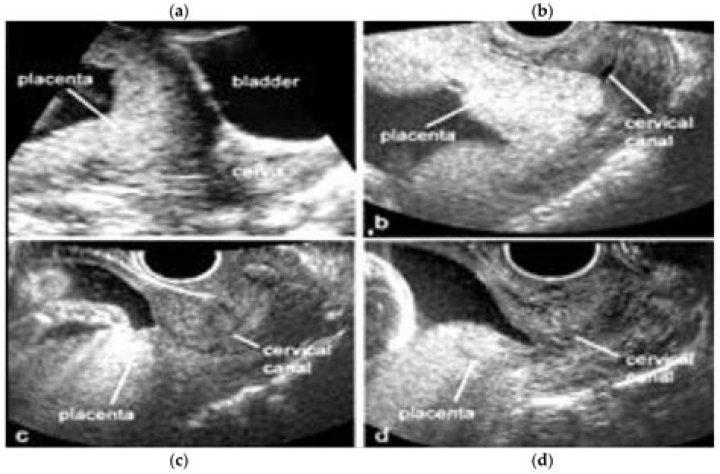

Cervical funnelling is a sign of cervical incompetence and represents the dilatation of the internal part of the cervical canal and reduction of the cervi...